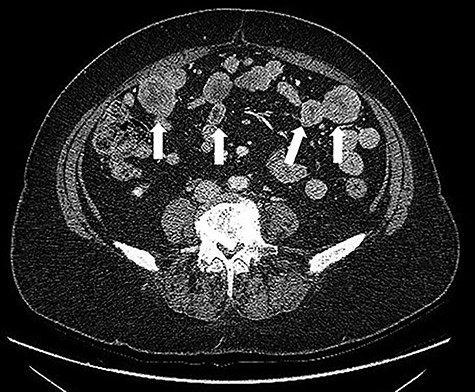

A 68-years-old woman (body mass index 35.6) was admitted with recent onset sideropenic anemia and not heart-related angina pectoris. At physical examination, a slightly mobile mass in the left iliac fossa was palpable. Carcinoembryonic antigen, carbohydrate antigen 19.9 (CA 19.9) carcinoma antigen 125 (CA 125) were normal. Upper and lower GI endoscopy were negative for any lesion. The patient was submitted for computed tomography (CT) scan, showing multiple solid density processes with colliquation areas in the abdominal cavity (Fig. 1). The greatest mass (8.0 × 5.6 cm) was located in the pelvis in close contact with the uterine fundus and the small bowel (Fig. 2). Cranially to this process, at least 20 other tumors with a diameter between 0.8 and 3.8 cm could be appreciated.

CT scan: Bulky (8.0 × 6.5 cm) mass located in the pelvis in close contact with the uterine fundus.